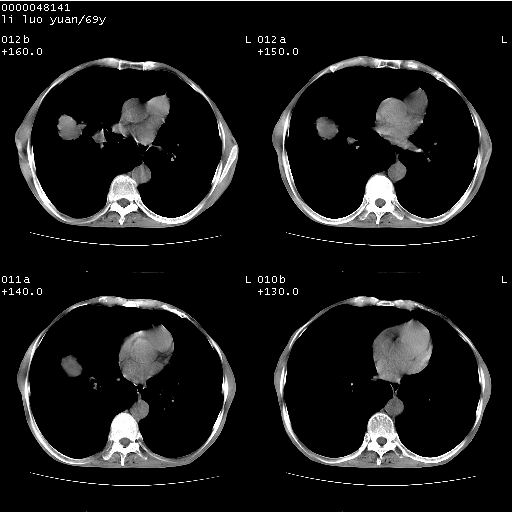

临床资料:老年患者,咯血、消瘦

影像表现:桶状胸,双肺纹理纤细、紊乱,透过度增高,肺野内可见多发、散在、大小不等的无壁高透过影,右肺中叶外侧段分叶样软组织占位,左上肺纤维索条样密度影,相应层面左侧胸腔轻度萎陷,纵隔左移。

影像诊断:1、慢支、肺气肿、双下肺野肺大泡形成

2、左上肺陈旧性肺结核

3、右肺中叶外侧段占位 考虑肺ca可能性较大、建议增强及痰检脱落细胞

诊断:1、慢支、肺气肿、纵隔疝形成、双下肺野肺大泡。

3、右肺占位 考虑肺ca可能性较大、建议增强及痰检脱落细胞